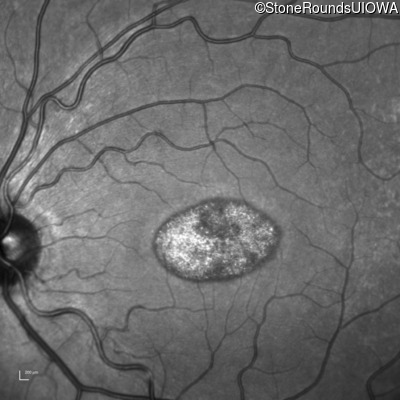

This 22 year old man had macular abnormalities noted incidentally at a routine eye exam at age 19. Since then, he has experienced a gradual loss of acuity particularly in the left eye.

| AR Stargardt Disease | ABCA4 | Tyr245Stop TAT>TAG | Unknown | AR |